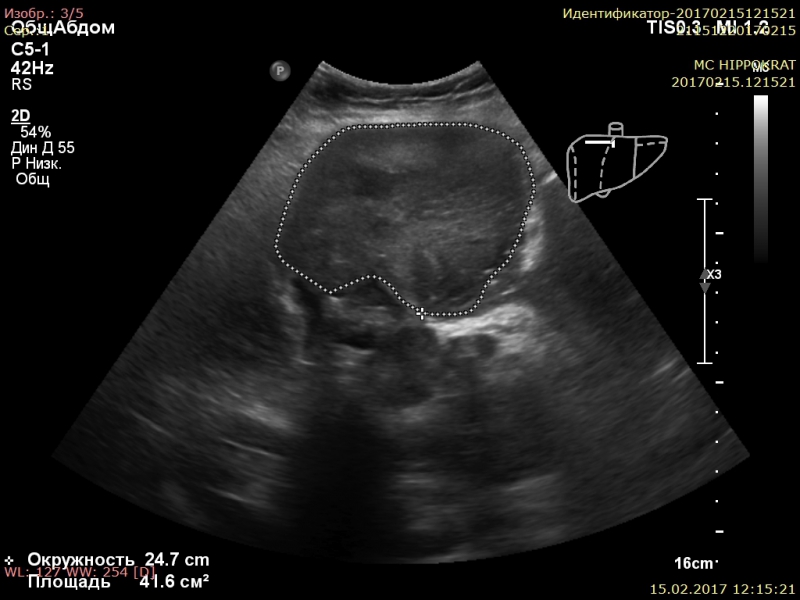

Диагностика опухоли почки на УЗИ

В нескольких исследованиях изучалась дифференциация подтипов опухолей почек с использованием УЗИ . Рисунок 5: На этом снимке показано различие во внешнем виде и усилении структуры светлоклеточного и папиллярного почечно-клеточного рака .

Ультразвуковая диагностика рака почек . УЗИ почек и надпочечников не только помогает диагностировать различные заболевания этих Рак почки - очень серьезное заболевание, которое можно вылечить на ранних стадиях . Пиелонефрит имеет более благоприятный прогноз . . .